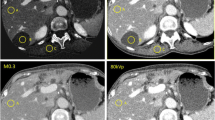

The mean attenuation values of 80 kVp- and 140 kVp images for hypervascular hepatic lesions in the arterial phase were 119.3 ± 33.5 HU and 77.5 ± 16.6 HU, respectively. On averaged images attenuation was 91.7 ± 21.3 HU. This was significantly different from 80-kVp- and 140-kVp images (p <0.001 for both comparisons, Fig. 1). All other anatomical regions (liver, fat, aorta, muscle, air) differed significantly when the three datasets were compared (Table 1).

Contrast-enhanced CT images obtained with a preset soft-tissue window (window width, 350 HU; window level, 50 HU) in a 64-year-old man with hepatocellular carcinoma. 140-kVp images (a), 80-kVp images (b) and averaged images (c) generated with dual-energy CT. 80-kVp images (b) show a hypervascular lesion, which is not identified on corresponding 140 kVp-images (a) and averaged images (c). There are other hypervascular liver lesions in the right and left lobe of the liver which also represent tumor

The number of detected lesions on 80-kVp, 140-kVp and averaged images was 3.4 ± 1.3, 1.4 ± 1.1, and 2.6 ± 1.2, respectively. These differences were significant (Table 2).

This study demonstrates the feasibility of contrast-enhanced dual-energy CT for detection of hypervascular liver lesions in patients with hepatocellular carcinoma. Higher detection rates are based on higher attenuation of iodine in the low-kVp images in comparison to 140-kVp and averaged 120-kVp equivalent images. Hypervascular liver lesions had significantly higher attenuation values on 80-kV images than on averaged and 140-kVp images which correlates with the results of other studies [21, 22]. This also leads to a higher lesion-to-liver ratio. Because there is increased photoelectric absorption at 80 kVp relative to the absorption at 140 kVp and 120 kVp, contrast material has higher attenuation at lower peak voltage. This ultimately may enable better depiction of small lesions or, alternatively, a smaller amount of contrast material to be injected at similar detection rates [21]. Our data are supported by the findings of Nakayama et al. who reported that the amount of contrast material can be reduced by at least 20% without degradation in image quality when reducing the tube voltage from 120 kV to 90 kV [23]. In addition, in this study imaging obtained with low tube voltage led to a reduction in radiation dose by as much as 57%. Decreasing the tube voltage and the iodine concentration of the contrast material particularly would benefit patients who may need to undergo multiple CT examinations, young patients who are at increased risk of developing cancer from medical radiation exposure [24], or those patients with renal impairment.

Although the image quality of 80-kVp, 140-kVp and averaged images differs significantly when assessed qualitatively, there was no statistical difference in contrast-to-noise and signal-to-noise ratios between 80-kVp and averaged images. However, between 80-kVp and 140-kVp images differences in qualitative assessment of image quality were significant. An increase in image noise may not represent a clinical problem for the detection of hypervascular liver lesions due to a high lesion-to-liver ratio, but it remains to be determined whether higher noise will adversely affect the interpretation of other anatomical or pathological phenomena in the upper abdomen. An option would be specific techniques to reduce image noise in the setting of low kVp images. Kalra et al. reported on noise reduction filters that effectively helped to reduce the noise on CT images acquired with a radiation dose reduced by 50% without compromising image quality. Their filters were developed to compensate for the degradation of image quality that results from the increased noise that accompanies the use of reduced tube current [28–30].